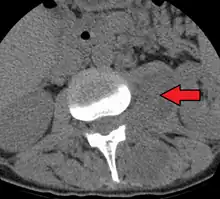

Psoas abscess

Paraspinal abscess in the psoas muscle

Psoas abscess is a collection of pus in the iliopsoas muscle compartment.[1][2] It can be classified into primary psoas abscess (caused by hematogenous or lymphatic spread of a pathogen) and secondary psoas abscess (resulting from contiguous spread from an adjacent infectious focus).[2]

Psoas abscess may be caused by lumbar tuberculosis. Owing to the proximal attachments of the iliopsoas, such an abscess may drain inferiorly into the upper medial thigh and present as a swelling in the region. The sheath of the muscle arises from the lumbar vertebrae and the intervertebral discs between the vertebrae. The disc is more susceptible to infection, from tuberculosis and Salmonella discitis. The infection can spread into the psoas muscle sheath.[3]